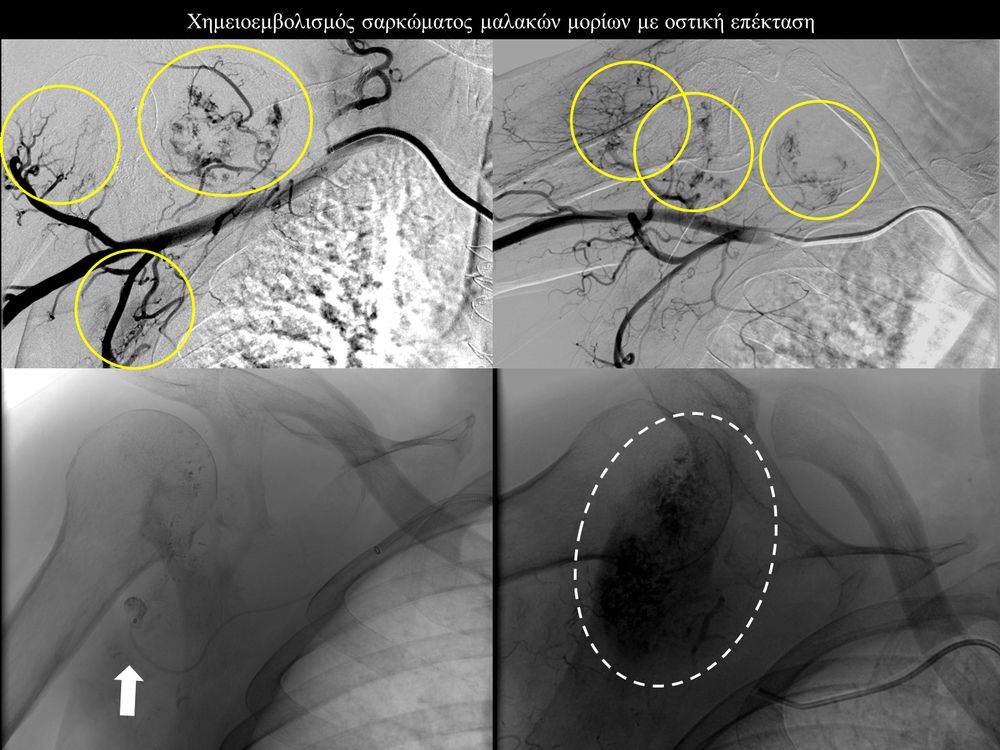

Ενδείξειςαποτελούν επίσης το χολαγγειοκαρκίνωμα και οι μεταστάσεις από καρκίνο του μαστού, καρκίνωμα νεφρού και σαρκώματα μαλακών μορίων.